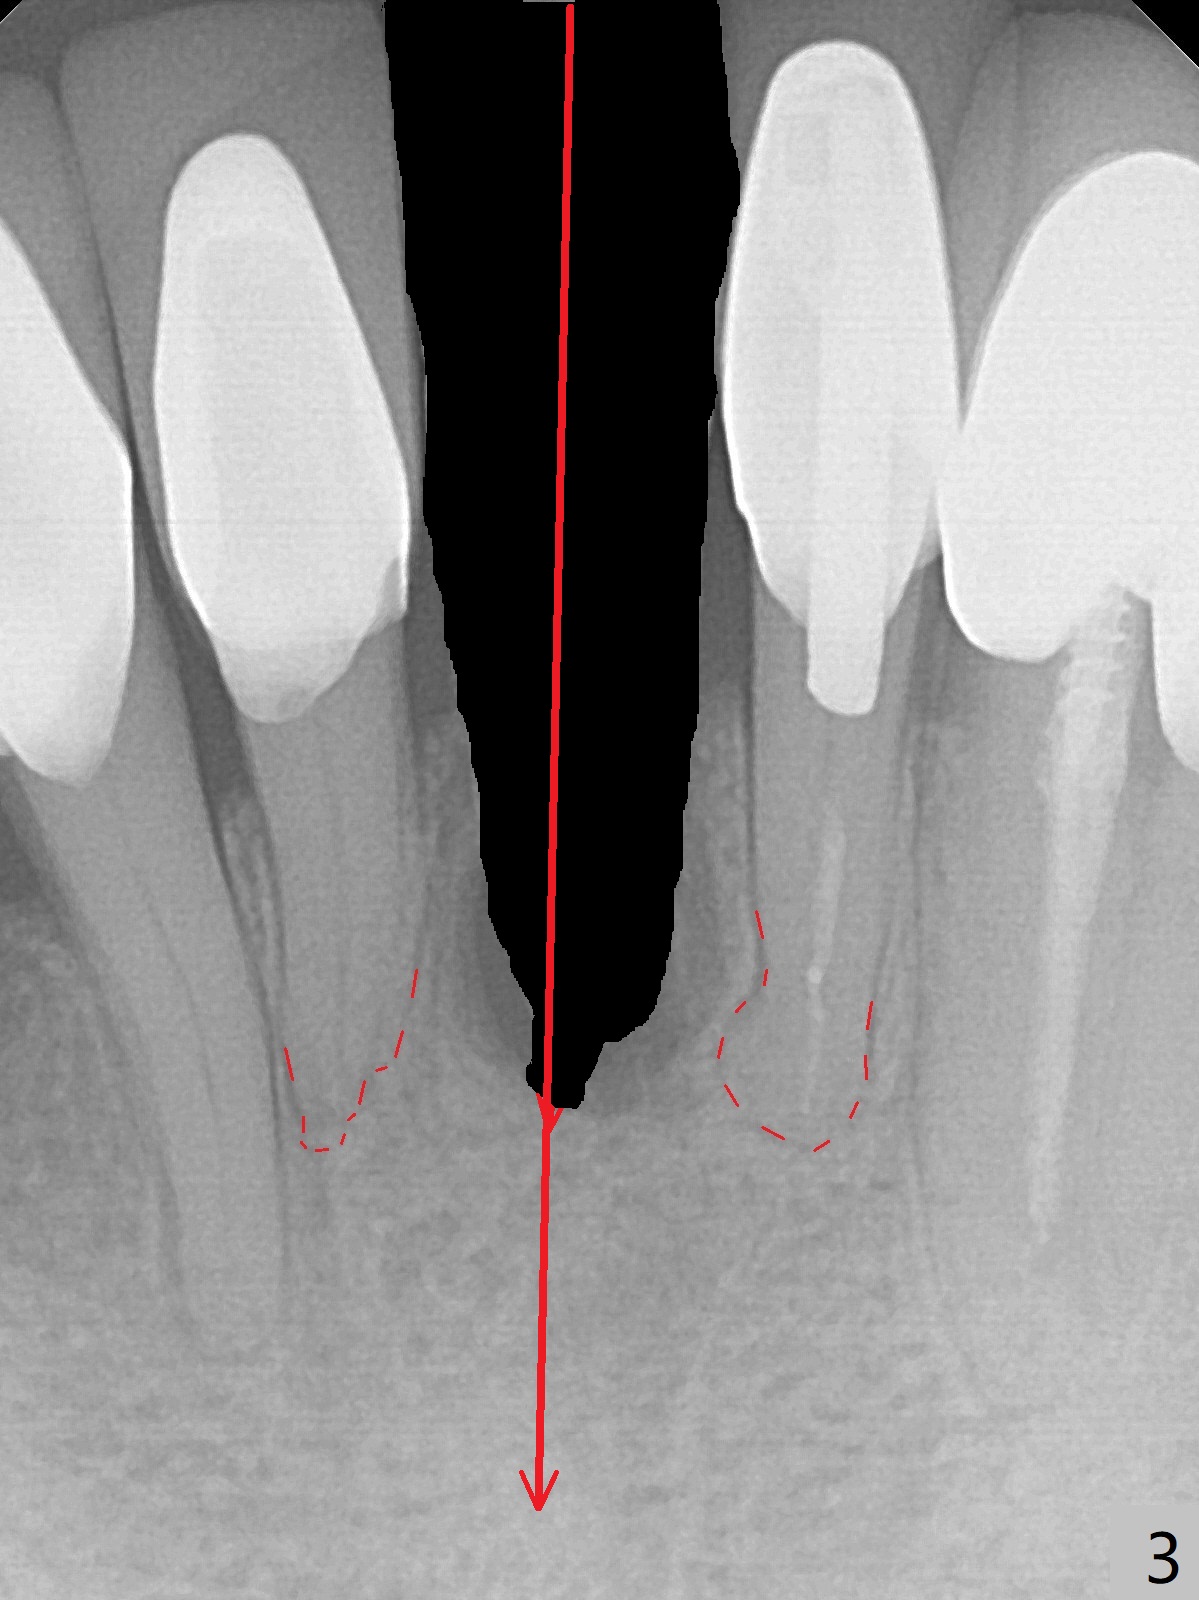

A 74-year-old man finally agrees to have the tooth #24 to be extracted for immediate implant with 3-year mobility and buccal shift (occlusal trauma or root fracture, Fig.0,1). Because of curved root tips of the neighboring teeth (Fig.1 red dashed line), the initial osteotomy will be created mesially (Fig.2 red arrow), followed by change in trajectory (Fig.3). The initial depth will be 14 mm (gingival level; ~ 12 mm bone level (easy change in trajectory and/or position). PA will be taken. The implant will be 2.5x14 mm (Fig.4).